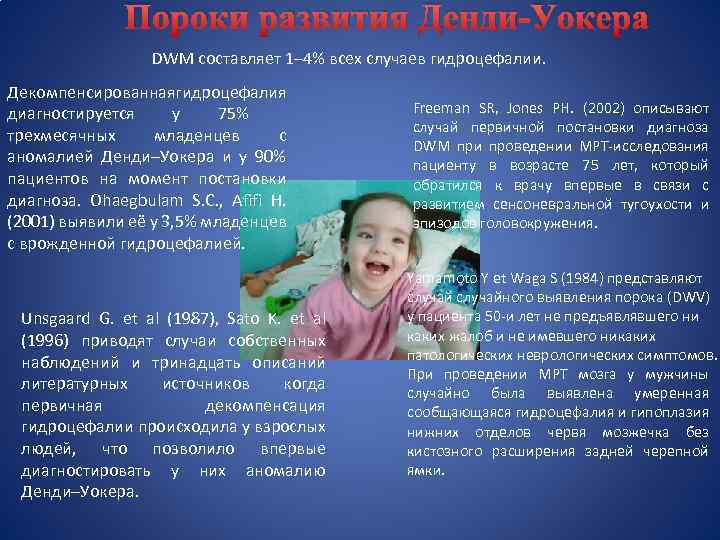

МРТ снимки мальформации Денди-Уокера